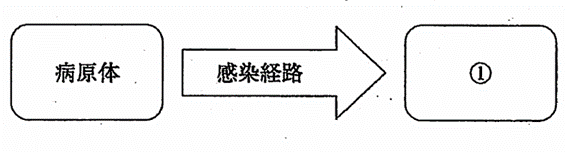

感染成立の3要因を図に示す。①への対策はどれか。1つ選べ。

a.隔離

b.検疫

c.予防接種

d.マスクの着用

解答を見る

c